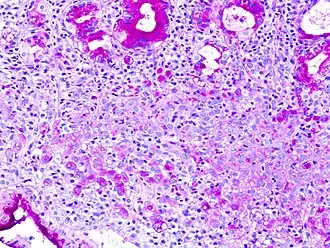

Periodic acid–Schiff (PAS) is a staining method used to detect polysaccharides (such as glycogen) and mucosubstances (such as glycoproteins, glycolipids and mucins) in tissues. The reaction of periodic acid oxidizes vicinal diols in these sugars, usually breaking up the bond between two adjacent carbons not involved in the glycosidic linkage or ring closure in the ring of monosaccharide units that are part of the long polysaccharides and creating a pair of aldehydes at the two free tips of each broken monosaccharide ring. The oxidation condition has to be sufficiently regulated so as to not further oxidize the aldehydes. These aldehydes then react with the Schiff reagent to give a purple-magenta color. A suitable basic stain is often used as a counterstain.

PAS staining is mainly used for staining structures containing a high proportion of carbohydrate macromolecules (glycogen, glycoprotein, proteoglycans), typically found in e.g. connective tissues, mucus, the glycocalyx, and basal laminae.

PAS staining can be used to assist in the diagnosis of several medical conditions: